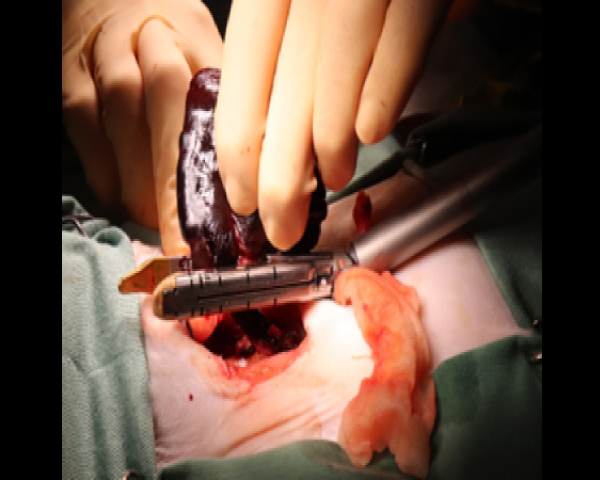

開腹手術にて腫瘤を摘出